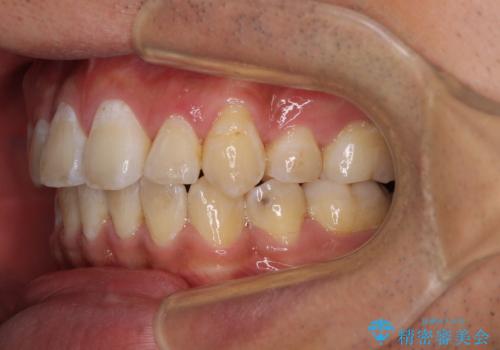

- 前歯の叢生と八重歯を気にして来院された患者様です。

叢生が強く、奥歯の咬合も左右差が大きかったため、上下左右4本を抜歯して、ワイヤー矯正を行うこととしました。

奥歯の咬み合わせを改善したいため、治療期間が長くなりましたが、患者様には辛抱強くお付き合いいただきました。

上下の正中を合わせることもでき、患者様には大変満足していただきました。